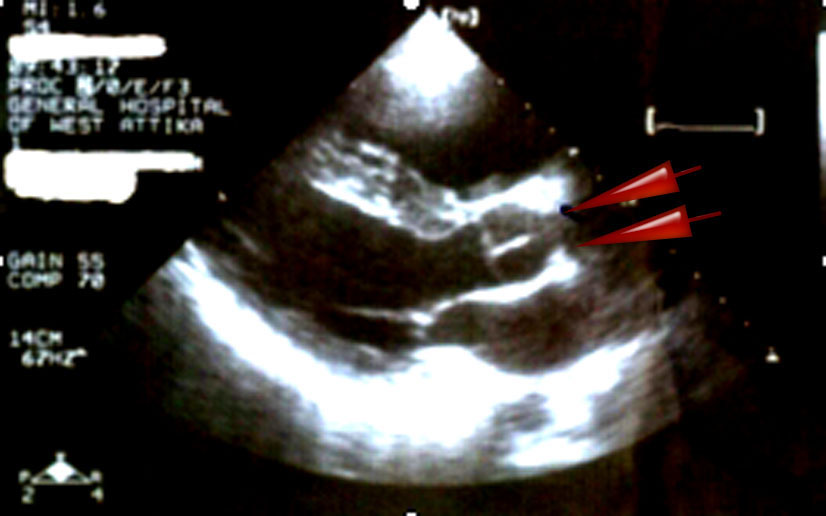

We present a case of a 28 years old male with delayed diagnosis of a severe supravalvular aortic stenosis accompanied with peripheral pulmonary artery stenosis and increased right ventricular pressure. The patient had been diagnosed since he was 3 years old to suffer from pulmonary artery hypertension of idiopathic origin. The diagnosis was made by tranthoracic echocardiography and magnetic resonance imaging.